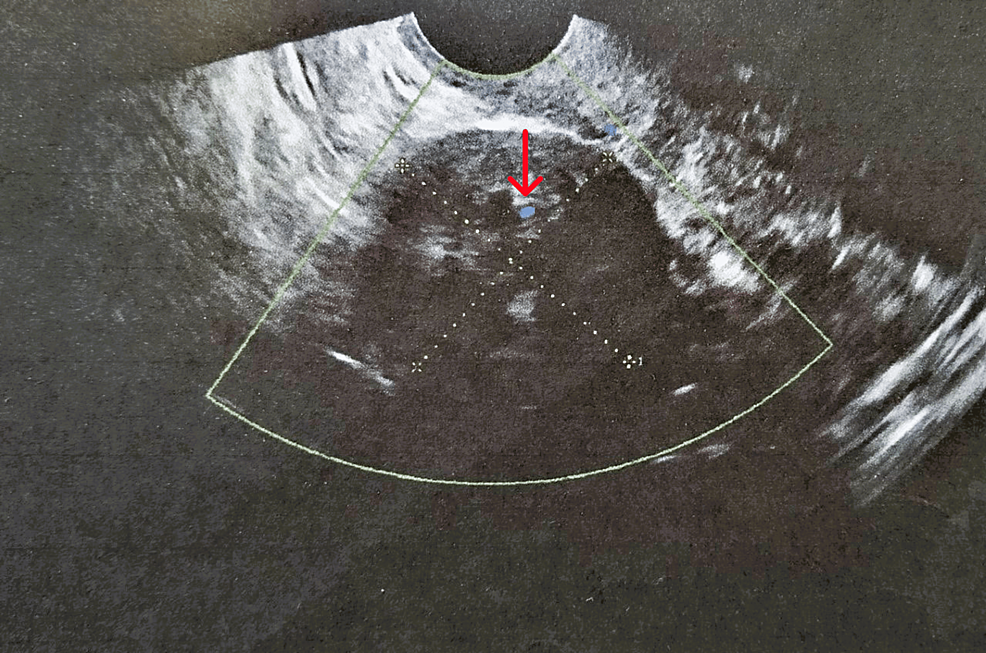

Surgical Treatment of a Rare Case of Ovarian Fibroma Associated With Elevated CA125 Levels in a Patient of Reproductive Age: A Case Report

Small ovarian fibromas (< 10cm) associated with elevated serum CA125 levels are rarely encountered, particularly in women of reproductive age. We report a rare case diagnosed in a 35-year-old patient...

Discussion: The preoperative differential diagnosis of ovarian fibromas from uterine pedunculated subserosal leiomyomas or malignant ovarian tumors remains difficult and in some cases may be impossible.